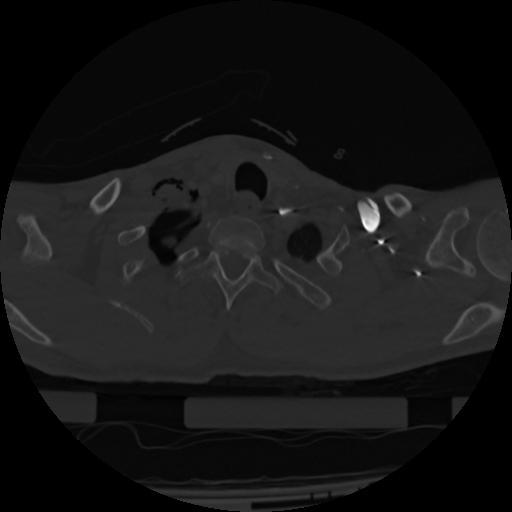

22 ANGIO,CE,Vol,0.5,ANGIO,,